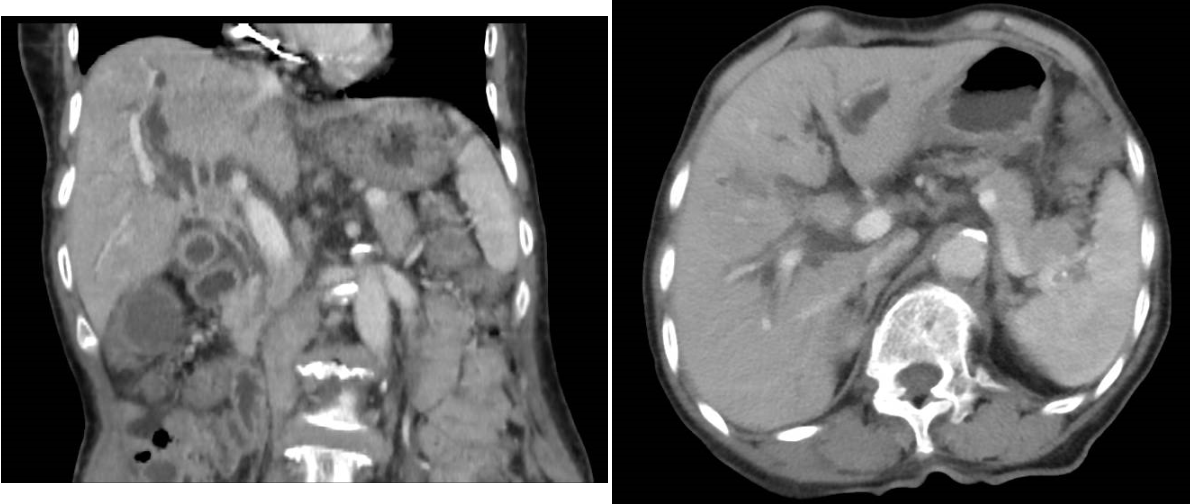

患者,女,79岁,因皮肤、巩膜黄染,尿色加深3天就诊于色情导航 。入院总胆红素高达422umol/L,肝脏增强MRI提示:肝总管/胆囊管汇合处肿物,考虑恶性,并继发肝内胆管扩张。该患高龄,肿瘤位于肝门部,手术风险大,出血几率高,且家属不同意行外科治疗。MDT会诊后,拟先行DSA引导下胆道活检联合胆道支架植入术,为后续治疗创造机会。

孙志强反复阅片后分析该患病情:梗阻部位处于肝总管、胆囊管交汇处,属高位胆管梗阻,不宜行内镜下逆行胆管引流术(ERCP),可行经皮肝穿刺胆管引流术(PTCD),再根据胆管造影情况来判断能否行胆道支架置入术。在明确患者没有手术禁忌症后,于CT导引下行PTCD,后于DSA导引下行胆管造影。因胆管梗阻严重,造影后无法通过,即便利用导丝导引也十分困难。经过反复尝试和更换不同硬度导丝后,终于导丝越过梗阻部位,导丝导引导管成功完成胆道造影,明确了梗阻的部位和长度,最终顺利完成了本次胆道支架置入手术。

术后第2天,患者皮肤、巩膜黄染缓解,尿色变浅。1周后患者胆汁引流量明显减少,总胆红素降至98 umol/L。再次分析病情后,复查胆道造影见造影剂顺利通过狭窄部位并进入十二指肠,证实胆道通畅,拔除胆道引流管。同时术中利用胆道活检毛刷进行刷检,成功刷取胆道病变组织一块,送病理回报:考虑恶性,倾向腺癌。最终明确诊断为:胆管癌,为接下来的抗肿瘤治疗提供了可靠的证据。